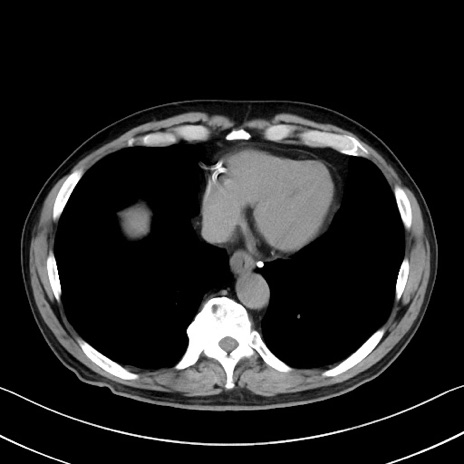

症例35(横断像)

【症例】70歳代 男性

【主訴】腹部膨満、嘔吐

【現病歴】昨日より腹部膨満感出現。本日増悪し、仙痛出現。嘔吐あり、受診。

【既往歴】糖尿病、胆摘後

【身体所見】BP 149/80mmHg、HR 74/min、BT 35.9℃、腹部:膨満、軟、圧痛なし。腸雑音減弱あり。上腹部正中切開瘢痕あり。

【データ】WBC 13500、CRP 1.72